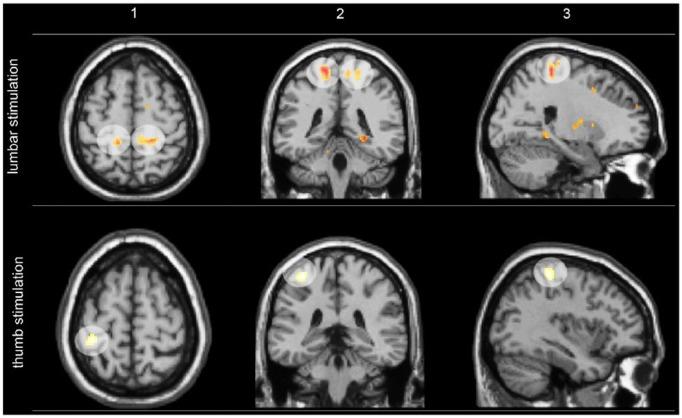

Motor control, which relies on constant communication between motor and sensory systems, is crucial for spine posture, stability and movement. Adaptions of motor control occur in low back pain (LBP) while different motor adaption strategies exist across individuals, probably to reduce LBP and risk of injury. However, in some individuals with LBP, adapted motor control strategies might have long-term consequences, such as increased spinal loading that has been linked with degeneration of intervertebral discs and other tissues, potentially maintaining recurrent or chronic LBP. Factors contributing to motor control adaptations in LBP have been extensively studied on the motor output side, but less attention has been paid to changes in sensory input, specifically proprioception. Furthermore, motor cortex reorganization has been linked with chronic and recurrent LBP, but underlying factors are poorly understood. Here, we review current research on behavioral and neural effects of motor control adaptions in LBP. We conclude that back pain-induced disrupted or reduced proprioceptive signaling likely plays a pivotal role in driving long-term changes in the top-down control of the motor system via motor sensory cortical reorganization. In the outlook of this review, we explore whether motor control adaptations are also important for other (musculoskeletal) pain conditions.